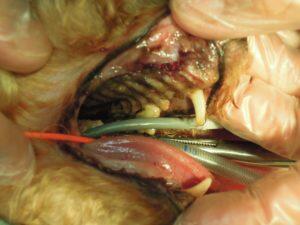

6.歯周病のため右側上顎の歯を全て抜歯し、

7.右側下顎の歯も骨折に注意して抜歯し、